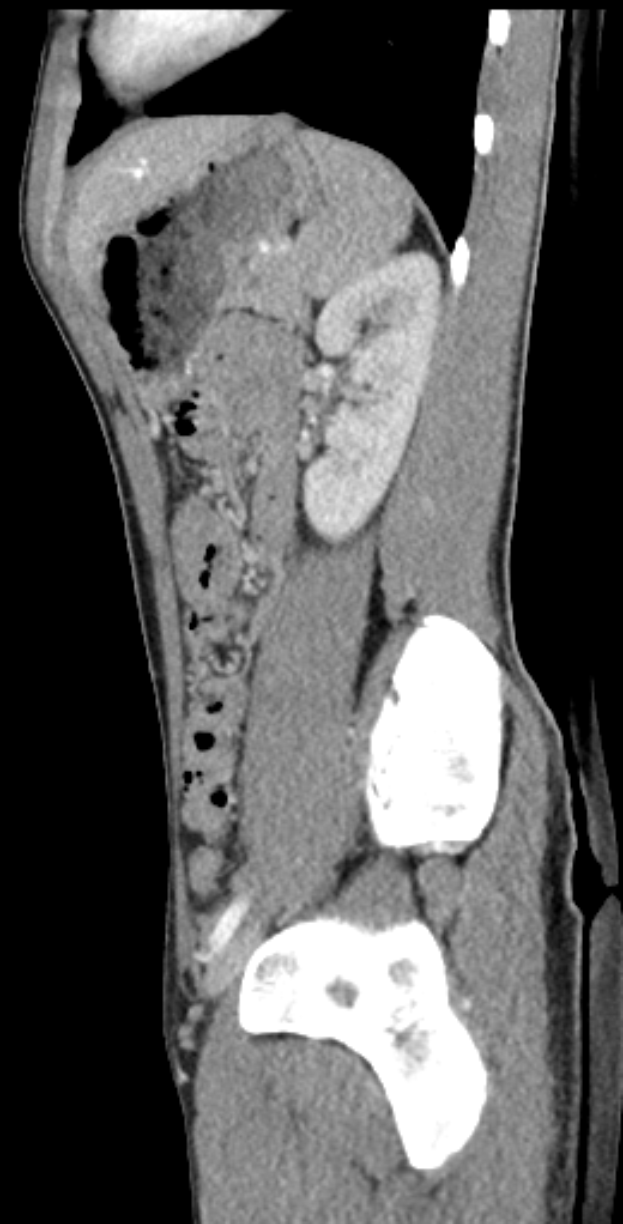

Eine MRT-Aufnahme eines Knies, die einen Riss in der Mitte zeigt, umgeben von einem dunklen Hintergrund.Adeline Schmiedecke

Bei Jan Thielmann begannen die Beschwerden bereits vor dem Anpfiff. Er hatte mindestens einen Tag zuvor über muskuläre Probleme geklagt. Während des Aufwärmtrainings verschlimmerte sich die Situation, sodass er abbrechen musste. Eine anschließende MRT-Untersuchung bestätigte die Muskelverletzung, woraufhin Eric Martel seine Position in der Startelf übernahm.